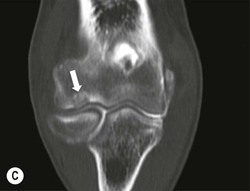

The capitellum is the third most commonly affected site in osteochondritis dissecans (after the knee and ankle). It commonly affects teenagers and young adults. A focal osteochondral fragment or defect may be visualised on radiographs. Cross-sectional imaging with MRI, MR arthrography or CT arthrography is used to detect radiographically occult lesions and for grading osteochondral lesions (Fig. 46-21). The osteochondral fragment may remain in situ or lie remotely within the elbow joint. Fluid SI at the base of the osteochondral lesion on MRI, or contrast medium tracking around the fragment on arthrographic images, is a sign of an unstable lesion. Integrity of the overlying articular cartilage is a good sign of stability.